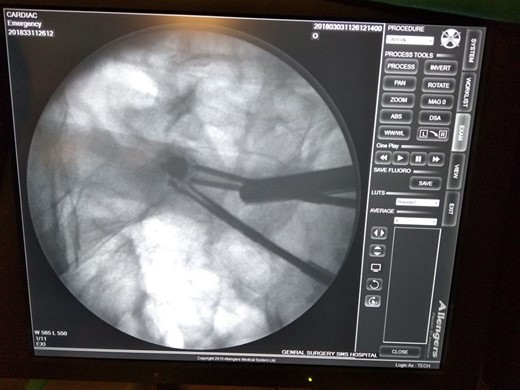

Retained video capsule removed (Fig. 3) and stricturoplasty done extracorporeally by taking out the loop through an incision in right iliac region. Patient discharged on Day 7 with liquid diets. Post-operative picture of patient (Fig. 4).